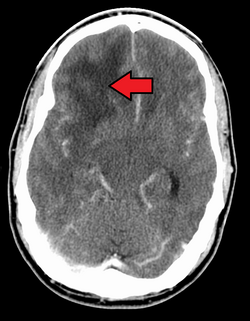

GBM in the frontal right lobe as seen on CT scan

When viewed with MRI, glioblastomas often appear as ring-enhancing lesions. The appearance is not specific, however, as other lesions such as abscess, metastasis, tumefactive multiple sclerosis, and other entities may have a similar appearance.[59] Definitive diagnosis of a suspected GBM on CT or MRI requires a stereotactic biopsy or a craniotomy with tumor resection and pathologic confirmation. Because the tumor grade is based upon the most malignant portion of the tumor, biopsy or subtotal tumor resection can result in undergrading of the lesion. Imaging of tumor blood flow using perfusion MRI and measuring tumor metabolite concentration with MR spectroscopy may add diagnostic value to standard MRI in select cases by showing increased relative cerebral blood volume and increased choline peak, respectively, but pathology remains the gold standard for diagnosis and molecular characterization.[citation needed]